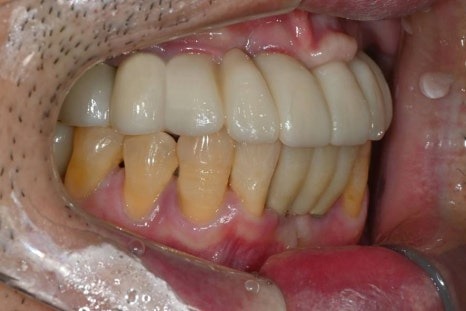

임시치아부터 최종 보철까지의 과정

수술 직후에는

임시틀니 대신 고정형 임시치아를 적용하여

일상생활과 식사 불편을 최대한 줄였습니다.

· 수술 다음 날 임시치아 장착

· 하악 일부는 2개월 내 조기 보철 완성

· 상악은 뼈이식 안정화를 충분히 거쳐 진행

전신질환이 있어

치료 기간이 길어질 가능성도 고려했으나,

6개월 내 안정적으로

보철을 마무리할 수 있었습니다.